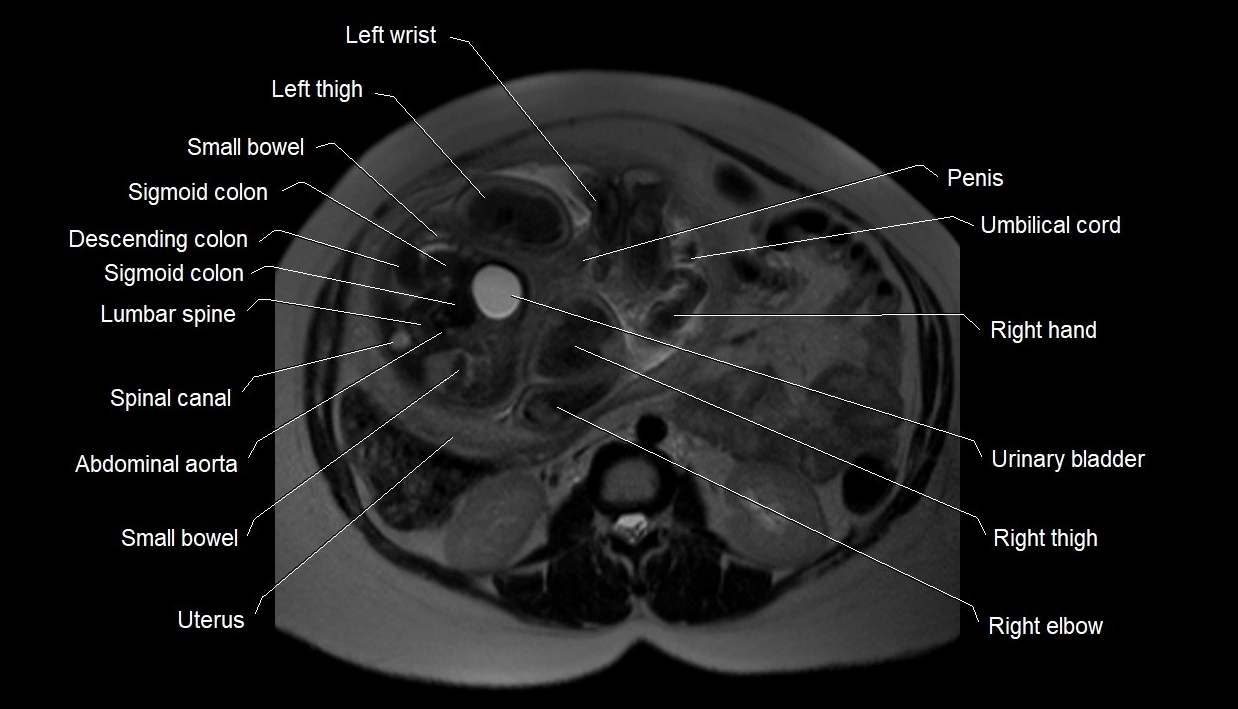

Amniotic fluid is the protective liquid surrounding the fetus within the amniotic sac. It plays an essential role in cushioning the fetus, enabling fetal movement, maintaining temperature stability, and allowing for normal lung and musculoskeletal development.

The volume and composition of amniotic fluid change throughout pregnancy. It is mainly derived from maternal plasma in early pregnancy, while in later stages, it consists largely of fetal urine, lung secretions, and transmembrane exchanges.

• Imaging relevance: MRI used for fetal visualization and assessing oligohydramnios/polyhydramnios when ultrasound is inconclusive

MRI Appearance

T2 HASTE (T2 GRE):

• Amniotic fluid shows very bright hyperintense signal

• Provides natural contrast against fetus and placenta

• Small particles (vernix) may appear as scattered hypointense foci within bright fluid